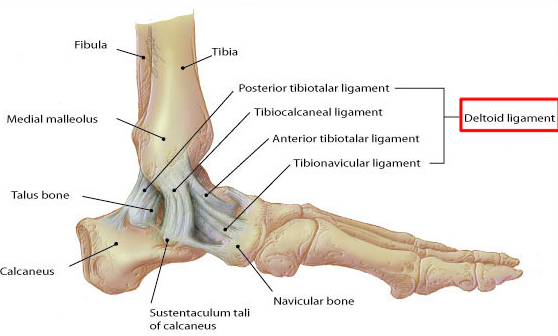

Describe the location and function of the medial ligament (deltoid ligament) of the malleolus

Identify the different ligaments composing the medial ligament of the malleolus